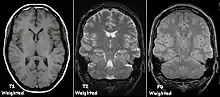

T1 and T2

Each tissue returns to its equilibrium state after excitation by the independent relaxation processes of T1 (spin-lattice; that is, magnetization in the same direction as the static magnetic field) and T2 (spin-spin; transverse to the static magnetic field). To create a T1-weighted image, magnetization is allowed to recover before measuring the MR signal by changing the repetition time (TR). This image weighting is useful for assessing the cerebral cortex, identifying fatty tissue, characterizing focal liver lesions, and in general, obtaining morphological information, as well as for post-contrast imaging. To create a T2-weighted image, magnetization is allowed to decay before measuring the MR signal by changing the echo time (TE). This image weighting is useful for detecting edema and inflammation, revealing white matter lesions, and assessing zonal anatomy in the prostate and uterus.

The standard display of MR images is to represent fluid characteristics in black and white images, where different tissues turn out as follows: